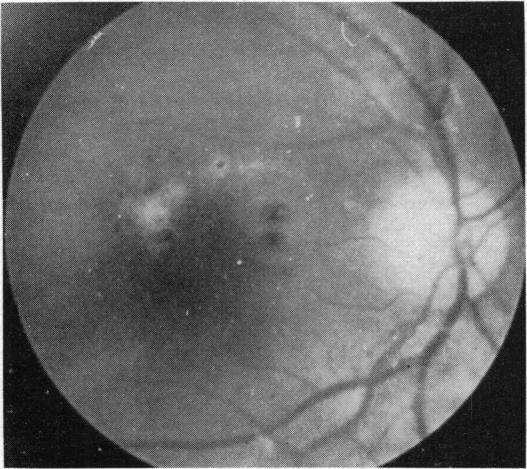

Toxoplasmic retinochoroiditis.